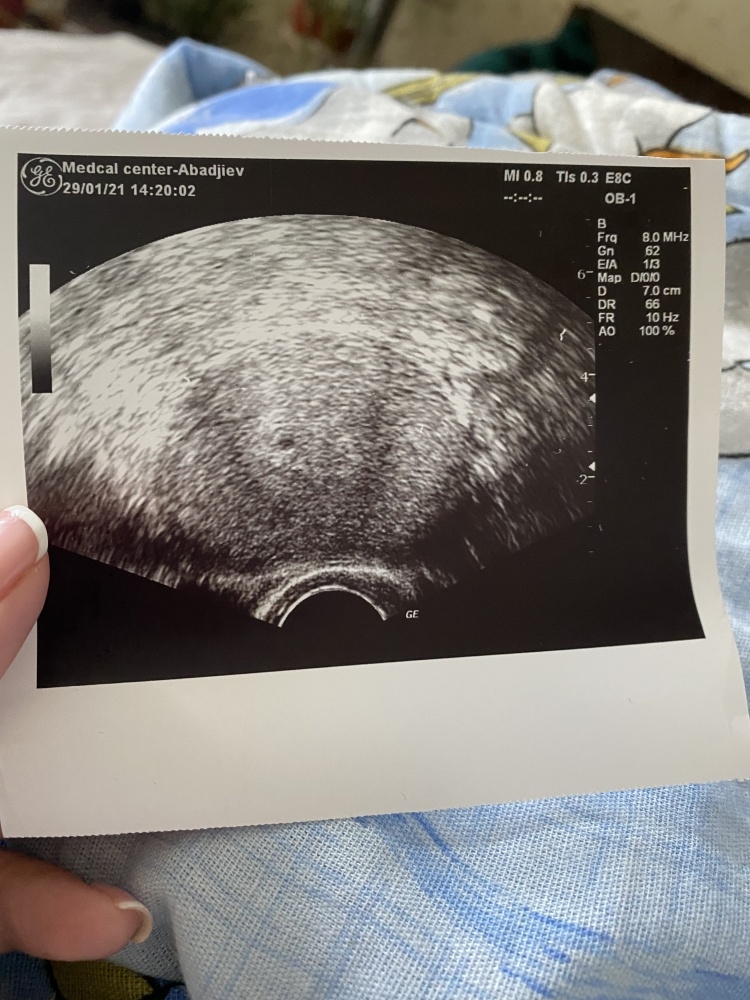

• y1wkxjzwvlhu.jpeg

Das foto ist von heute, der neue Arzt hat es sofort mit sein usgerät gesehen ( das haben die anderen zwei nicht) ist wie gesagt noch sehr klein aber hoffentlich wird alles besser😍

• Also bei mir sah es auch so aus in der 6. Woche :-) und am Foto würde ich auch auch sagen dass es genau passend aussieht.

Dann war ich am 29.1 bei anderem Arzt und er hat das wieder gesehen und meiner Meinung nach war das auch ein bisschen größer als am 27.1... er meinte aber es kann wirklich sein das ich Fehlgeburt habe aber wir werden auf jeden fall versuchen die Schwangerschaft zu retten